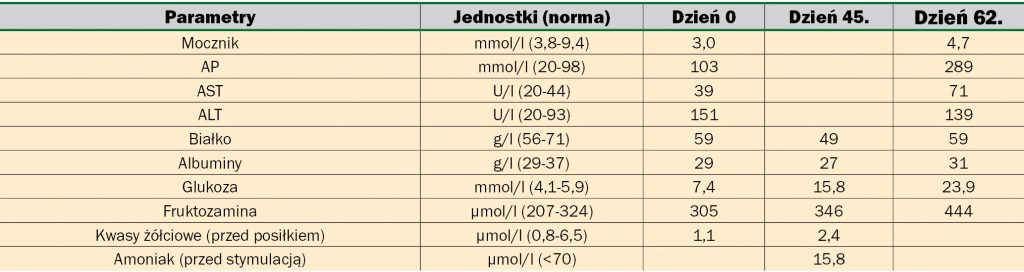

W oparciu o diagnostykę różnicową przeprowadzono szereg badań (tab. 1). Badanie cytologiczne skóry wykazało ropne zakażenie ziarniakami. W posiewach wyhodowano Staphylococcus intermedium. Badanie biochemiczne surowicy wykazało obniżony poziom mocznika oraz lekko podwyższone AP i ALT (tab. 2). W badaniu ultrasonograficznym jamy brzusznej, w wątrobie widoczne były obszary o średnicy do 15 mm otoczone przez mniej echogenne pasma, co przypominało wyglądem ser szwajcarski (ryc. 4), s. 30. Dodatkowo pobrano wiele próbek – bioptatów z chorobowo zmienionych miejsc na skórze. Naskórek był przerośnięty ze znacznym rogowaceniem warstwy powierzchownej o charakterze parakeratozy, z wakuolizacją keratynocytów w warstwie kolczystej i rozrostem komórek w warstwie podstawnej naskórka (ryc. 5, 6), s. 30. Opisanym zmianom towarzyszył rozproszony naciek komórek zapalnych (limfocytów i komórek plazmatycznych). Na tej podstawie postawiono wówczas rozpoznanie MEN, wtórnego ropnego zapalenia skóry oraz wyrównanego zapalenia wsierdzia zastawki mitralnej.